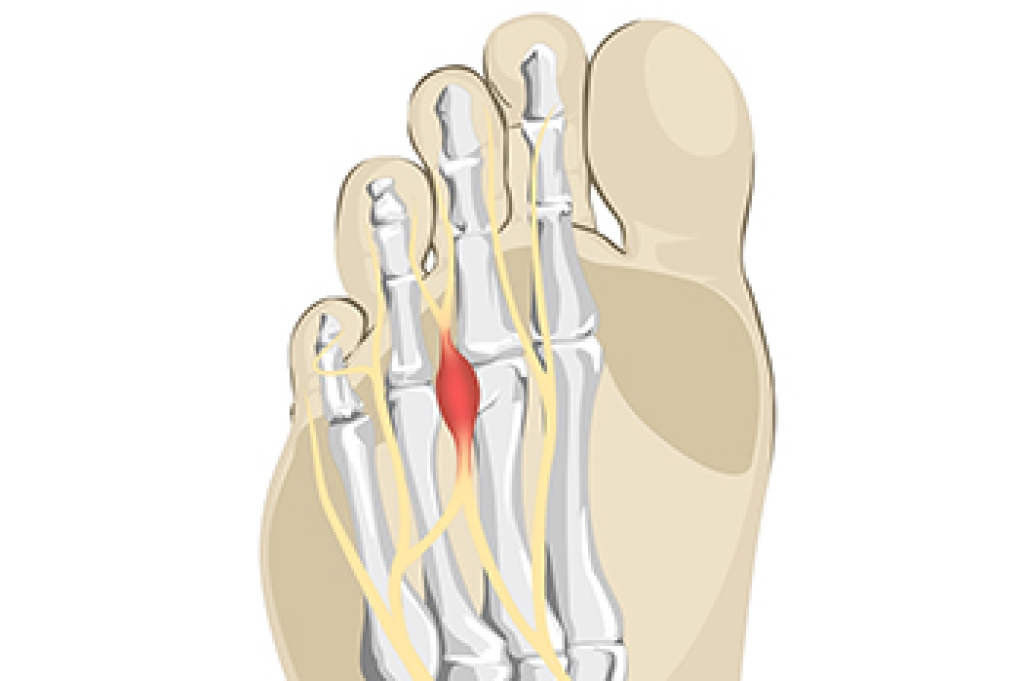

A plantar fibroma is a fibrous knot in the arch of the foot. It is embedded in the plantar fascia which is a band of tissue that extends from the heel to the toes along the bottom of the foot. There can be multiple plantar fibromas in the feet at the same time. There are no known causes for this condition. If you have a plantar fibroma, there will be a bump in the arch of your foot that cannot be missed. Any associated pain is most often due to a shoe rubbing against the nodule. Non-surgical options, such as steroid injections, physical therapy, and orthotics should be tried first. Surgery is a last resort and is the only thing that will remove a plantar fibroma entirely. Consult with a podiatrist for a proper diagnosis and to determine the treatment regimen that is right for you.

While there are no specific causes identified, a plantar fibroma can possibly come from genetic predisposition or the formation of scar tissue that forms from healing the tears in the plantar fascia.

There will be a noticeable lump in the arch of the foot that may or may not cause pain. If pain is felt, it is typically because a shoe is rubbing up against the lump or when walking or standing barefoot.

A plantar fibroma will not disappear without treatment, but it can get smaller and be a non-issue. If pain persists, a podiatrist examines the foot and when the arch of the foot is pressed, pain can be felt down to the toes. An MRI or biopsy might be performed to help diagnose or evaluate the plantar fibroma. The following non-surgical options are generally enough to reduce the size and pain of these nodules: